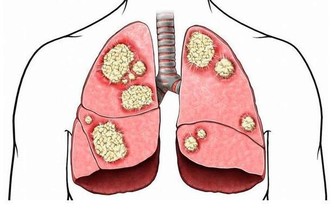

肺癌是“癌症之王”,是人類死亡的頭號殺手。肺癌的發病率男性多於女性,城市多於農村。

肺癌並非吸煙一族的專利,經常接觸二手煙、做飯的女性也是肺癌的高危人群。肺癌的致病因素比較複雜,空氣污染、環境因素、粉塵、刺激性氣味環境、遺傳史等等都是導致肺癌的致命因素,它就像一種慢性病一樣,在某種致病因素的長期刺激下,正常細胞會發生癌變,慢慢地形成腫瘤。據了解,閆懷禮在河北涿州拍攝一部叫《俏羅城》的電視劇。當地的蒼蠅、蚊子特別多,當時有一場戲拍戲的現場噴灑了很多敵敵畏,很多人都因為濃重的味道離開了,當時閆懷禮嗅覺不好感覺不到,長時間處在敵敵畏濃重的環境裡面,拍戲空擋還在那裡休息,好友六小齡童分析這是他患病的誘因之一,再加上多年拍戲工作太過勞累,閆懷禮才患上了肺癌。

據肺癌幫APP病例庫統計,小細胞肺癌約佔10%。小細胞肺癌,其癌細胞生長的速度快,轉移也迅速,且容易有抗藥性,大多為吸煙所引起,也與環境或基因有關。

肺腺癌約佔50%,以女性為主。肺腺癌為最常見的肺癌,也是不吸煙者(多數為女性的45歲以下)常見的類型,容易遠端轉移是其特徵。治療的原則得根據期別,通常一、二期可經由評估後進行手術,之後再做化療等。

鱗狀上皮細胞癌,約佔30%,吸煙男士居多。常常發生在男性吸煙者,早期多為局部向外延伸的轉移,後期則經由血路擴散。

患者人數約佔肺癌的5%,生長速度較快,會迅速經由血路及淋巴擴散,預後不佳。